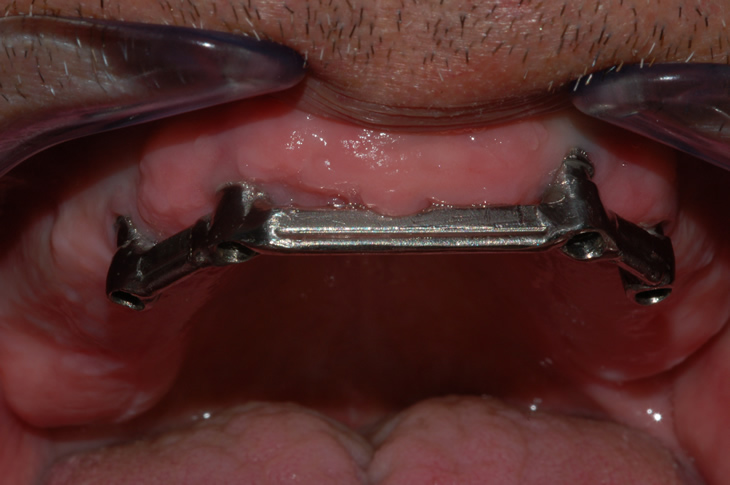

Per Overdenture si intende un sistema costituito da una protesi totale ancorata su impianti, composta da barre e controbarre.